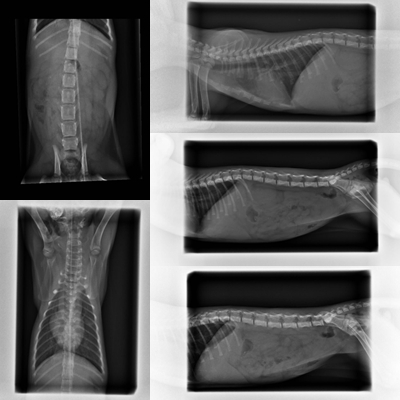

主題: 頭歪手腳不協調嚴重神經症狀的小六 申請者姓名: 陳露露 花色: 申請日期: 2014-03-06 17:53:51 申請者部落格: 申請者臉書網址: 所在縣市/合作醫院: 高雄市/恩澤動物醫院 治療費用: 10820元 需求人數: 13人 已結案 (2014-03-24 18:11:53) 報名人員: 頭頭媽(已付款)、蔡摳摳(已付款)、吳毓軒(已付款)、傻傻(已付款)、Cathy Kao(已付款)、阿貝(已付款)、Mrfl Ower(已付款)、sharonhuang9(已付款)、orange(已付款)、Michelle Lin(已付款)、周松兒(已付款)、Kerstin Lin(已付款)、林微利(已付款)、 候補人員: 動物病情說明: 有朋自遠方(北部)來訪,

公貓約4月齡0.5kg 35.8℃

小六身體虛弱失溫,雙側肺炎

雙眼葡萄膜炎,歪頭神經症狀

白血球暴增,眼鼻有上呼吸道症狀

醫生表示疾病部分先從病毒方面治療

住院期間再觀察神經症狀的狀況

因小六無食慾,上點滴補充營養及抗生素治療

因體虛失溫,醫院以紅外線燈罩維持溫度

上呼吸道部分,醫院每天視狀況噴霧治療

2/9小六一樣無法進食,因此點滴繼續維持,

2/10醫生試著以針筒少量緩慢灌食,一方面補充食物營養,

一方面觀察小六對食物的反應,及習慣進食的感覺,今天點滴換手了唷

2/12醫生表示小六終於能進食些許食物,但量極少,因此點滴依舊維持著,以補充不足的養分

2/13醫生表示小六進食量增加,但還需觀察

如隔天進食再顯進步,預計點滴可拆除

2/14今天點滴終於拆除嘍

小六進食狀況明顯進步,不過還是有些許流鼻水,醫生表示小六如保持進食正常及穩定狀態,兩天後即可出院,由志工帶回照顧並繼續觀察神經現象(一直偏右)及繼續治療上呼吸道部分

2/16醫生說小六這兩天食量已近正常,隔天可出院

2/17小六出院嚕,感謝杜專科所有醫生及助理的細心照顧

小六的醫療還需要大家的幫忙動物近況說明: 由志工帶回繼續觀察及照顧,待小六一切康復後,後續將會開放認養